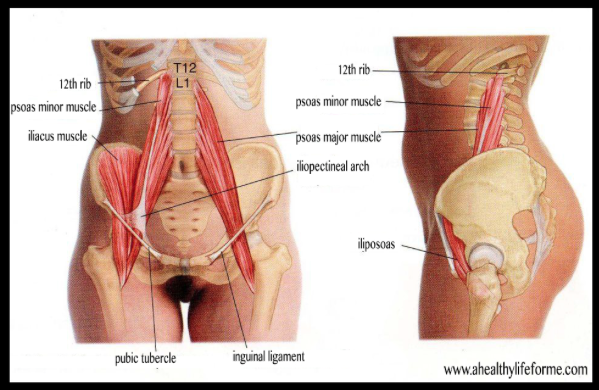

Psoas muscle release

You need to take a tennis/lacrosse ball and release your psoas muscles. (See figure 1)

To do this lay flat on your stomach and place ball 2-3 fingers to the left of your belly bottom and then 2-3 finger down from that point. So you should have made a right angle if you did this right. After you hold that trigger point for 5-10 minutes slowly come off/ roll off ball. Repeat for the right side.

Psoas muscle release

You need to take a tennis/lacrosse ball and release your psoas muscles. (See figure 1)

To do this lay flat on your stomach and place ball 2-3 fingers to the left of your belly bottom and then 2-3 finger down from that point. So you should have made a right angle if you did this right. After you hold that trigger point for 5-10 minutes slowly come off/ roll off ball. Repeat for the right side.